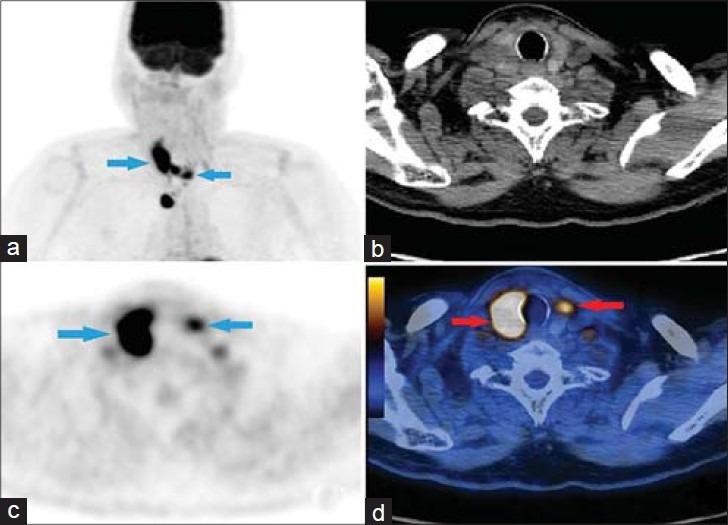

Two Cases of Thyroid Metastasis from Head and Neck Squamous Cell Carcinoma Detected by FDG-PET/CT.

We present two cases of head and neck squamous cell carcinoma (SCC) metastasizing to the thyroid gland. This is the first report that shows (18) F-fluorodeoxyglucose-positron emission tomography/computed tomography (FDG-PET/CT) images of tonsillar and supraglottic SCCs invading the thyroid gland. Alcohol and tobacco use are the two most important risk factors for head and neck cancers, but recently human papilloma virus (HPV) infection has become a significant risk factor in the United States. FDG-PET/CT is very useful for SCC staging/restaging and follow-up.